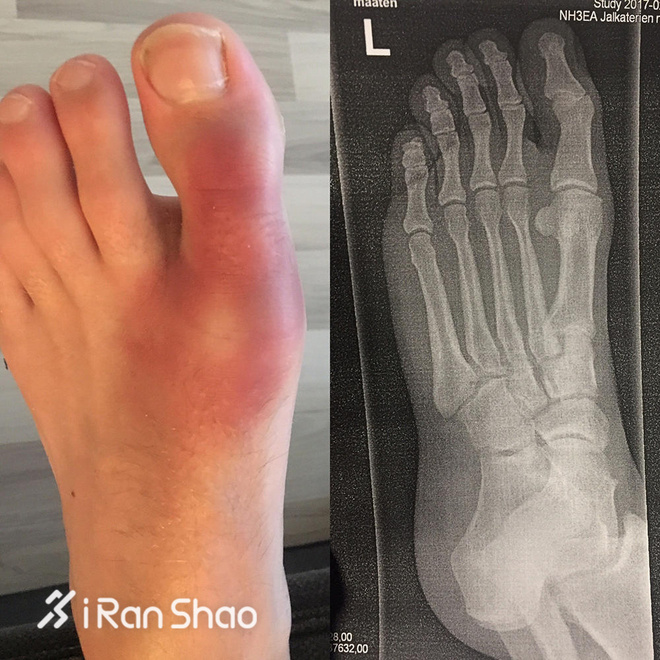

比赛结束之后,Runyon去检查了他的脚部,他以为自己的脚骨折了,不过X光显示并没有,医生告诉他,你这是“过度使用”。Runyon说,我不在乎我要花多长时间去完成,在最后一英里第一缕北极光闪现的时候,我的痛苦就消失了。